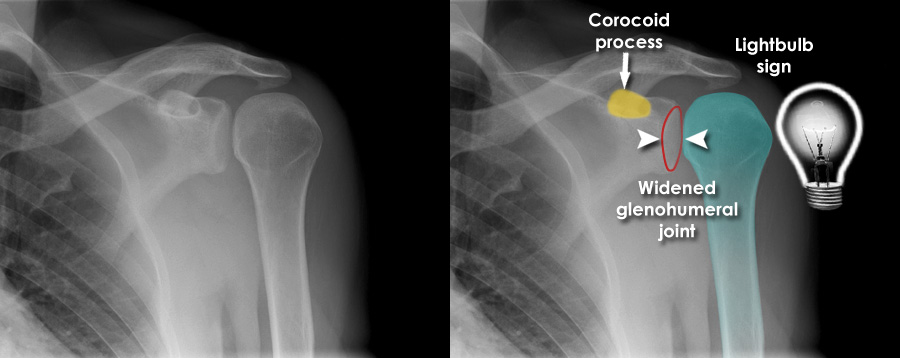

A 25-year-old man presents to the emergency department after falling on his outstretched left arm while playing rugby. He complains of severe pain in his left shoulder and inability to move the arm. On examination, the left shoulder appears flattened anteriorly with a prominent acromion, and the patient holds his arm slightly abducted and externally rotated. There is tenderness over the shoulder joint and limited range of motion due to pain. An X-ray of the left shoulder (see image) is performed.

Which of the following is the most likely diagnosis?

A) Left rotator cuff tear

B) Left anterior shoulder dislocation

C) Left clavicle fracture

D) Left proximal humerus fracture

E) Left posterior shoulder dislocation